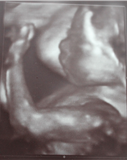

Silas Rosenbaum

* 24.01.2013 in Neckar Odenwald Kliniken Mosbach

† 24.01.2013